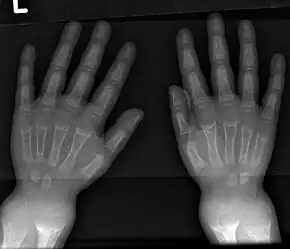

Widening of wrist

Wrist X-ray showing changes in rickets. Mainly cupping is seen here.

• Radiography typically show widening of the zones of provisional calcification of the metaphyses secondary to unmineralized osteoid. Cupping, fraying, and splaying of metaphyses typically appears with growth and continued weight bearing.[41] These changes are seen predominantly at sites of rapid growth, including the proximal humerus, distal radius, distal femur and both the proximal and the distal tibia. Therefore, a skeletal survey for rickets can be accomplished with anteroposterior radiographs of the knees, wrists, and ankles.[41]